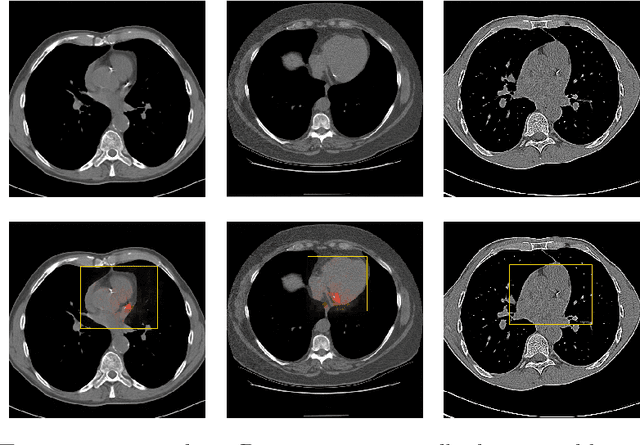

Abstract:Coronary artery calcium (CAC) burden quantified in low-dose chest CT is a predictor of cardiovascular events. We propose an automatic method for CAC quantification, circumventing intermediate segmentation of CAC. The method determines a bounding box around the heart using a ConvNet for localization. Subsequently, a dedicated ConvNet analyzes axial slices within the bounding boxes to determine CAC quantity by regression. A dataset of 1,546 baseline CT scans was used from the National Lung Screening Trial with manually identified CAC. The method achieved an ICC of 0.98 between manual reference and automatically obtained Agatston scores. Stratification of subjects into five cardiovascular risk categories resulted in an accuracy of 85\% and Cohen's linearly weighted $\kappa$ of 0.90. The results demonstrate that real-time quantification of CAC burden in chest CT without the need for segmentation of CAC is possible.